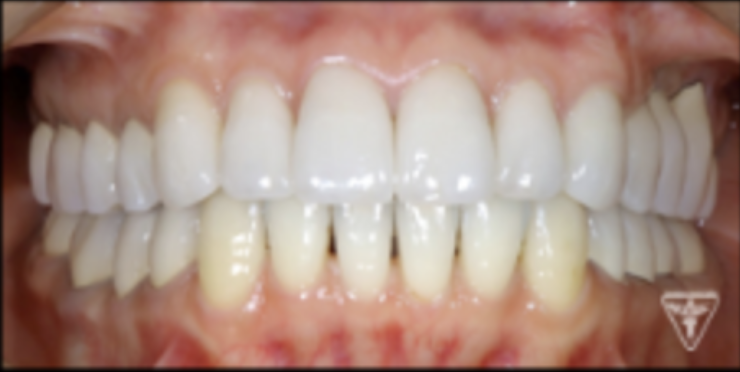

治療後

治療前後の比較